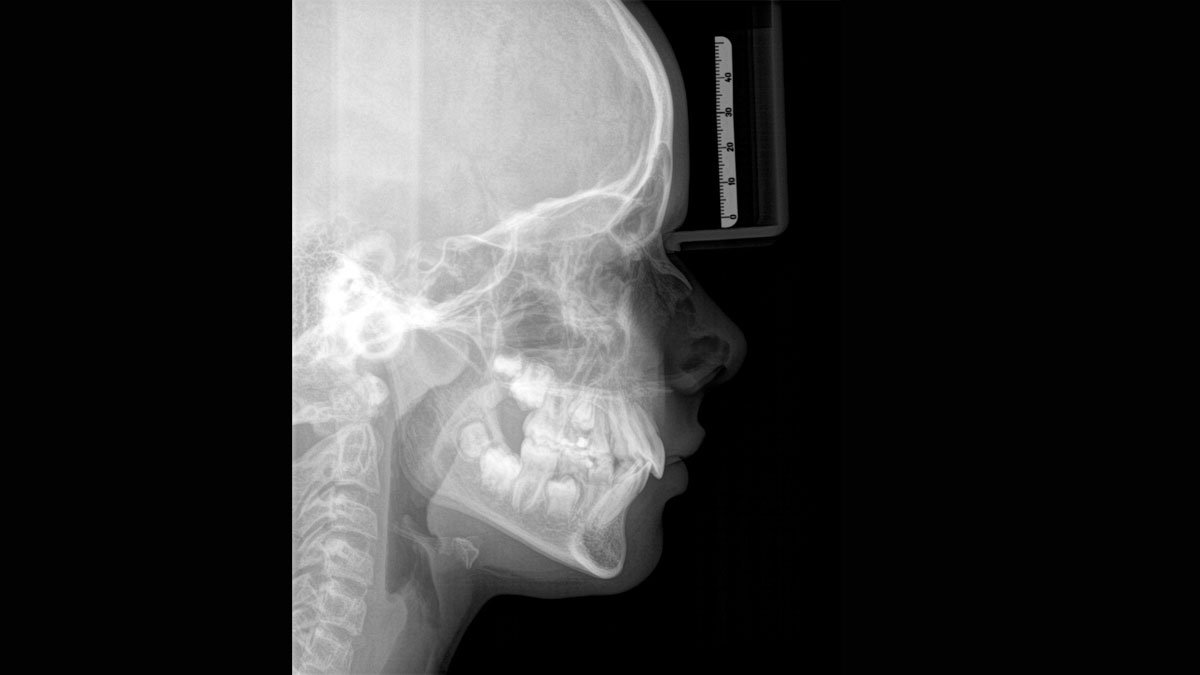

Axeos – the 2D/3D specialist system with a large volume and high image quality for practices with a broad treatment offering. Developed together with dentists and clinicians, Axeos provides the fullest range of functions out of all Dentsply Sirona extraoral X-ray devices. In addition to excellent image quality and tailor-made 3D volume sizes, the dental imaging device is fully optimised for enhanced patient comfort. Axeos not only provides quality in performance and comfort, but also with its award-winning design thanks to the integrated bite block accessory cabinet and ambient light.

For exceptional panoramic images with high sharpness. You can choose an optional right or left cephalometric arm, which can be retrofitted at any time